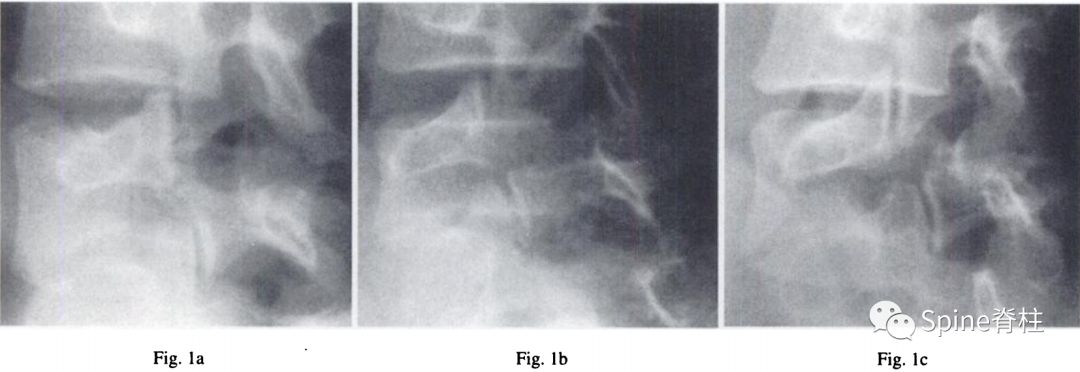

图:早期(a),进展期(b),终末期(c)

随后,Sairyo教授进一步CT研究,将Morita分型早期又分为 最早期 (very early): 骨折线模糊或不连续的骨折线和 晚早期 (late-early): 骨折线清晰明显。

图:腰5双侧峡部裂,右侧为 最早期 ,左侧为 晚早期